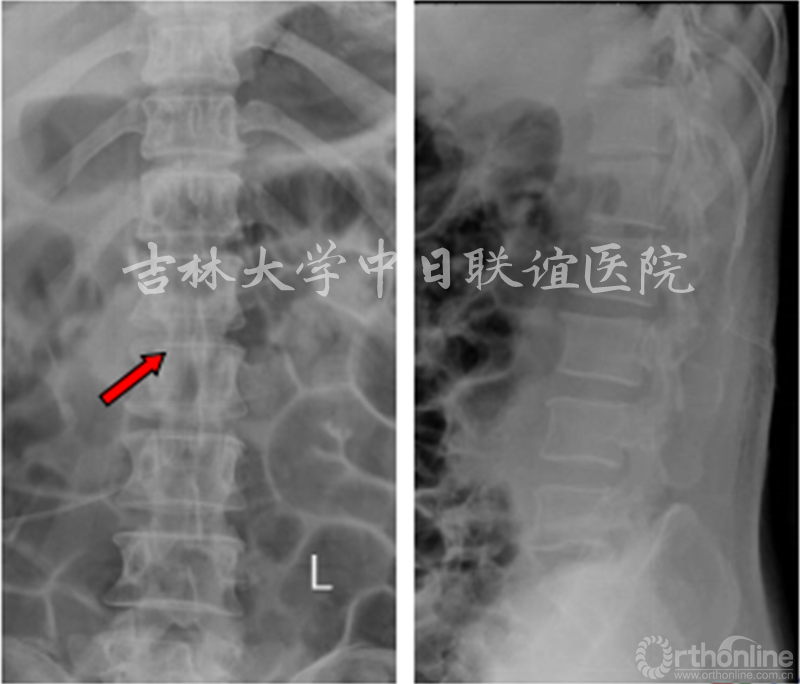

胸腰段X线/CT:未见明显异常

术后X线:

术后随访:

术后三天:术后右下肢疼痛消失,右下肢肌力较术前无明显改变。

术后2个半月:患者右下肢浅感觉较术前明显好转,右下肢各肌肉肌力大约IV级。